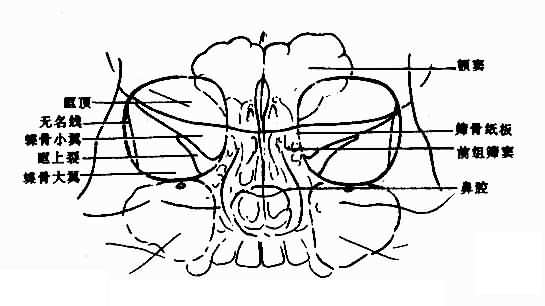

眼眶平片应观察:眶窝大小与形状,眶壁,包括眶顶、蝶骨小翼蝶骨大翼眶上裂筛骨纸板(图5-2-1)等和眶窝密度,上述表现在两侧眼眶基本对称。

正常眼眶

图5-2-1 正常眼眶(200后前位)